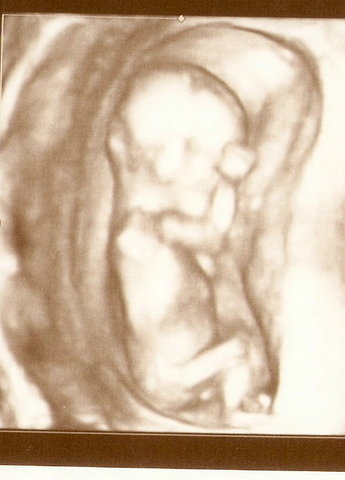

• УЗИ

9 недель

УЗИ

13 недель + 6 дней

предпологаемая дата рождения 21.01.2011

20 недень + 2 дня

предпологаемая дата родов 26.01.2011